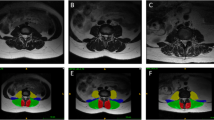

Recent studies have associated morphological and composition changes in paraspinal muscles with low back pain (LBP), which is the most common, but poorly understood musculoskeletal disorder in adults. Accurate paraspinal muscle segmentation from MRI is crucial to enable new image-based biomarkers for the diagnosis and prognosis of LBP. Manual segmentation is laborious and time-consuming. In addition, high individual anatomical variations also pose challenges, resulting in inconsistent segmentation across different raters. While automatic segmentation algorithms can help mitigate the issues, techniques that predict and visualize inter-rater segmentation variability will be highly instrumental to help interpret reliability of automatic segmentation, but they are rarely attempted. In this paper, we propose a novel multi-task TransUNet model to accurately segment paraspinal muscles while predicting inter-rater labeling variability visualized using a variance map of three raters’ annotations. Our technique is validated on MRIs of paraspinal muscles at four different disc levels from 118 LBP patients. Benefiting from the transformer mechanism and convolution neural networks, our algorithm is shown to perform better or similar to the state-of-the-art methods and a newly proposed multi-task U-Net model while predicting and visualizing multi-rater annotation variance per muscle group in an intuitive manner.